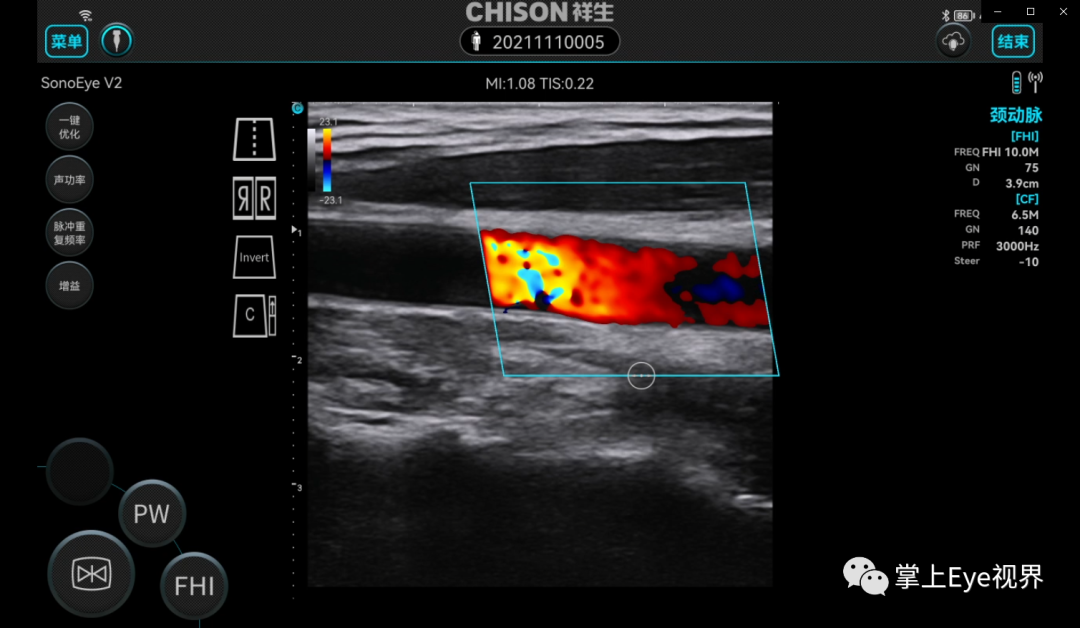

混叠

彩超伪像是什么超声基础 | 超声伪像_https://www.jmylbn.com_新闻资讯_第4张

掌超测颈动脉彩色血流模式